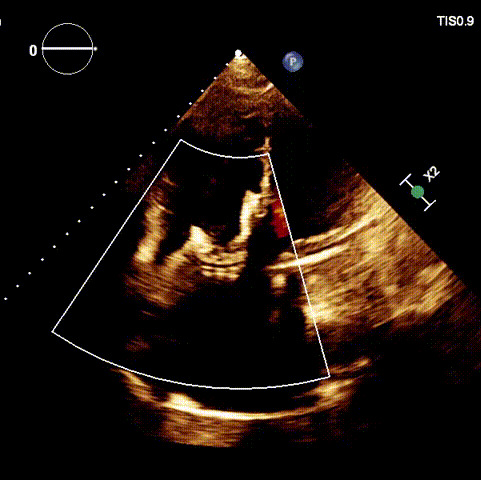

術(shù)后超聲

近日,廈門大學(xué)心血管病醫(yī)院王焱教授帶領(lǐng)的結(jié)構(gòu)性心臟病團(tuán)隊(duì),成功應(yīng)用LuX-Valve Plus經(jīng)血管三尖瓣置換系統(tǒng),為一例高危三尖瓣重度反流患者開展經(jīng)血管三尖瓣置換手術(shù)。此次手術(shù)系LuX-Valve Plus人工瓣膜在福建省的首例植入,手術(shù)過程順利,術(shù)后患者三尖瓣反流顯著改善,標(biāo)志著由葛均波院士團(tuán)隊(duì)作為主要研究者的LuX-Valve Plus經(jīng)血管三尖瓣置換系統(tǒng)全國(guó)多中心臨床研究的再一次成功實(shí)踐,為三尖瓣介入治療的醫(yī)學(xué)循證打下了夯實(shí)的基礎(chǔ)。 、

手術(shù)在全麻狀態(tài)下開展,海軍軍醫(yī)大學(xué)附屬長(zhǎng)海醫(yī)院陸方林教授與廈門心血管病醫(yī)院王焱院長(zhǎng)共同上臺(tái),為患者進(jìn)行手術(shù)。此次手術(shù)采用經(jīng)右側(cè)頸靜脈入路的方式將輸送器送入患者心臟內(nèi),在TEE及DSA引導(dǎo)下調(diào)整輸送器頭端角度,使得輸送器與三尖瓣瓣環(huán)平面垂直。在輸送器進(jìn)入右心室后釋放室間隔錨定裝置,而后釋放瓣葉夾持件(2個(gè)耳片結(jié)構(gòu))成垂直狀態(tài)。在TEE及DSA確定夾持件固定至三尖瓣葉根部且位于右室側(cè)后釋放人工瓣心房側(cè)盤片。隨后調(diào)整瓣膜同軸性以及室間隔錨定件位置(貼合室間隔),前推藏針管并固定,進(jìn)而釋放室間隔錨定裝置,并再次確認(rèn)瓣膜位置、穩(wěn)定性及同軸性,合攏輸送鞘后撤出輸送器,完成LuX-Valve Plus人工三尖瓣瓣膜的植入。